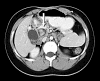

Image 1. Computed tomography image of upper abdomen revealing dilated extrahepatic bile duct with choledocholithiasis (arrow)